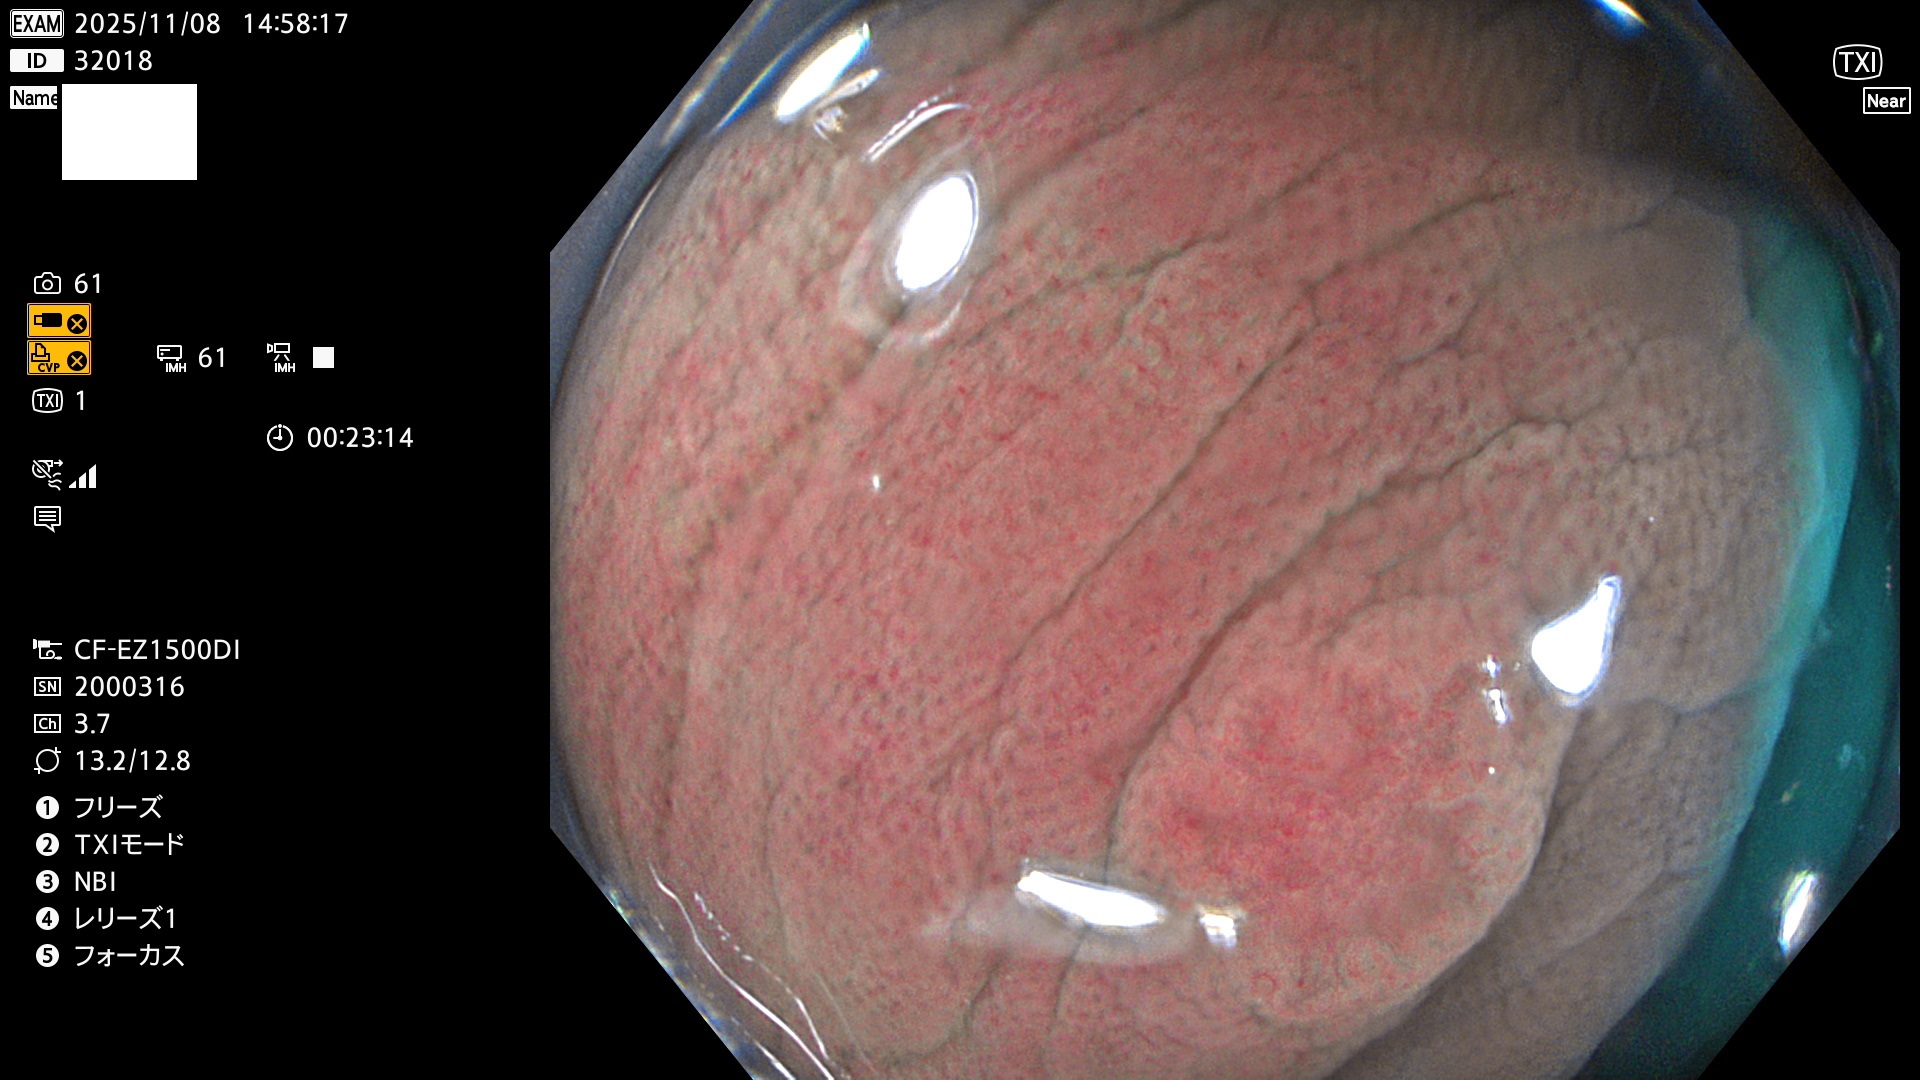

完全に平坦な物をUb、陥凹している物をUcと呼びます。Ubは認識が困難で、Ucはびらん(炎症)と紛らわしいために見落とされやすく、「内視鏡後・大腸癌」の原因になります。

専門的)Uc=De Novo癌? 内視鏡の解像度が低かった時代、このような説もありました。しかし今日の高精度内視鏡では良性の微小なUc型腺腫(APC遺伝子異常の腺腫)が日常的に見つかります。Ucこそが多段階発癌(Adenoma-Carcinoma Sequence)のMain Routeです。

2025年11月6日〜11月9日の4日間(40件)6個 (Uc_ADR=6個/40人=15%)